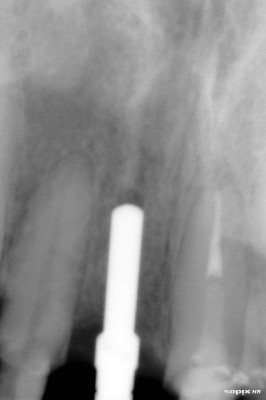

Radiografía inicial